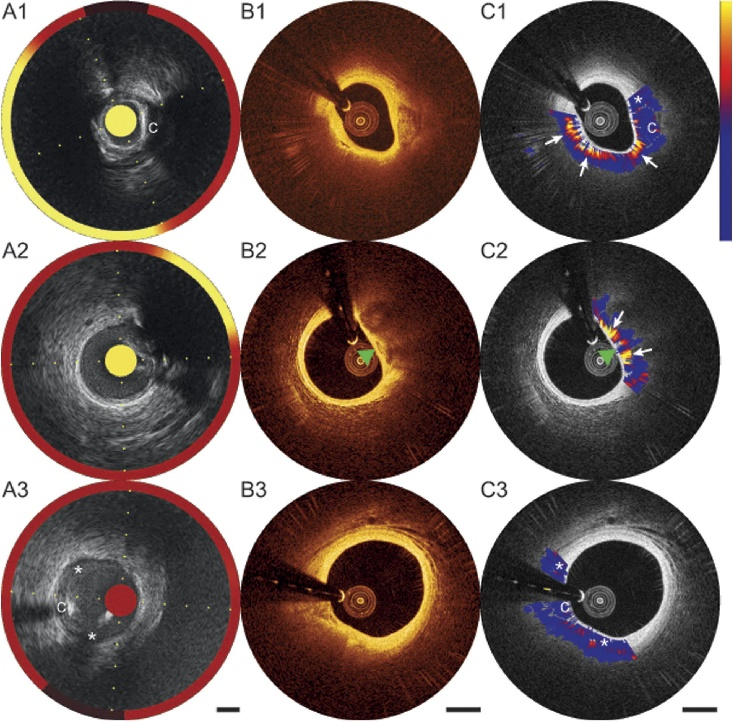

A1-A3:NIRS-IVUS,B1-B3:OCT,C1-C3:IPA

IPA与人工脂质评分有良好的相关性(r²>0.7)

IPA可以准确鉴别TCFA,且优于NIRS-IVUS(LCBI4mm

不同组织间光的衰减程度各不相同,IPA计算结果反映了OCT近红外光进入不同成分的斑块内形成的明暗梯度变化,按变化由弱至强的程度从蓝色到红色再到黄色进行染色标记。薄纤维帽脂质斑块、巨噬细胞、胆固醇结晶、斑块内出血等明暗变化强烈的结构较易被IPA识别为“阳性”,而纤维斑块、厚纤维帽脂质斑块等明暗变化较均匀的结构则易被识别为“阴性”。